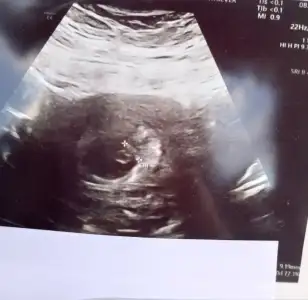

Teyzoşlar biz 7 haftalik olmuşuz tam ölçülerimizde uyuyor 🥰